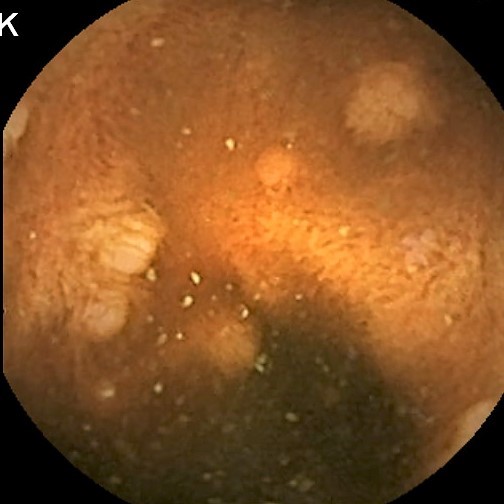

Capsule Endoscopy: Ileum Terminale, Lymphoid Hyperplasia

Capsule Endoscopy: Ileum Terminale, Lymphoid Hyperplasia. Just click on a picture!